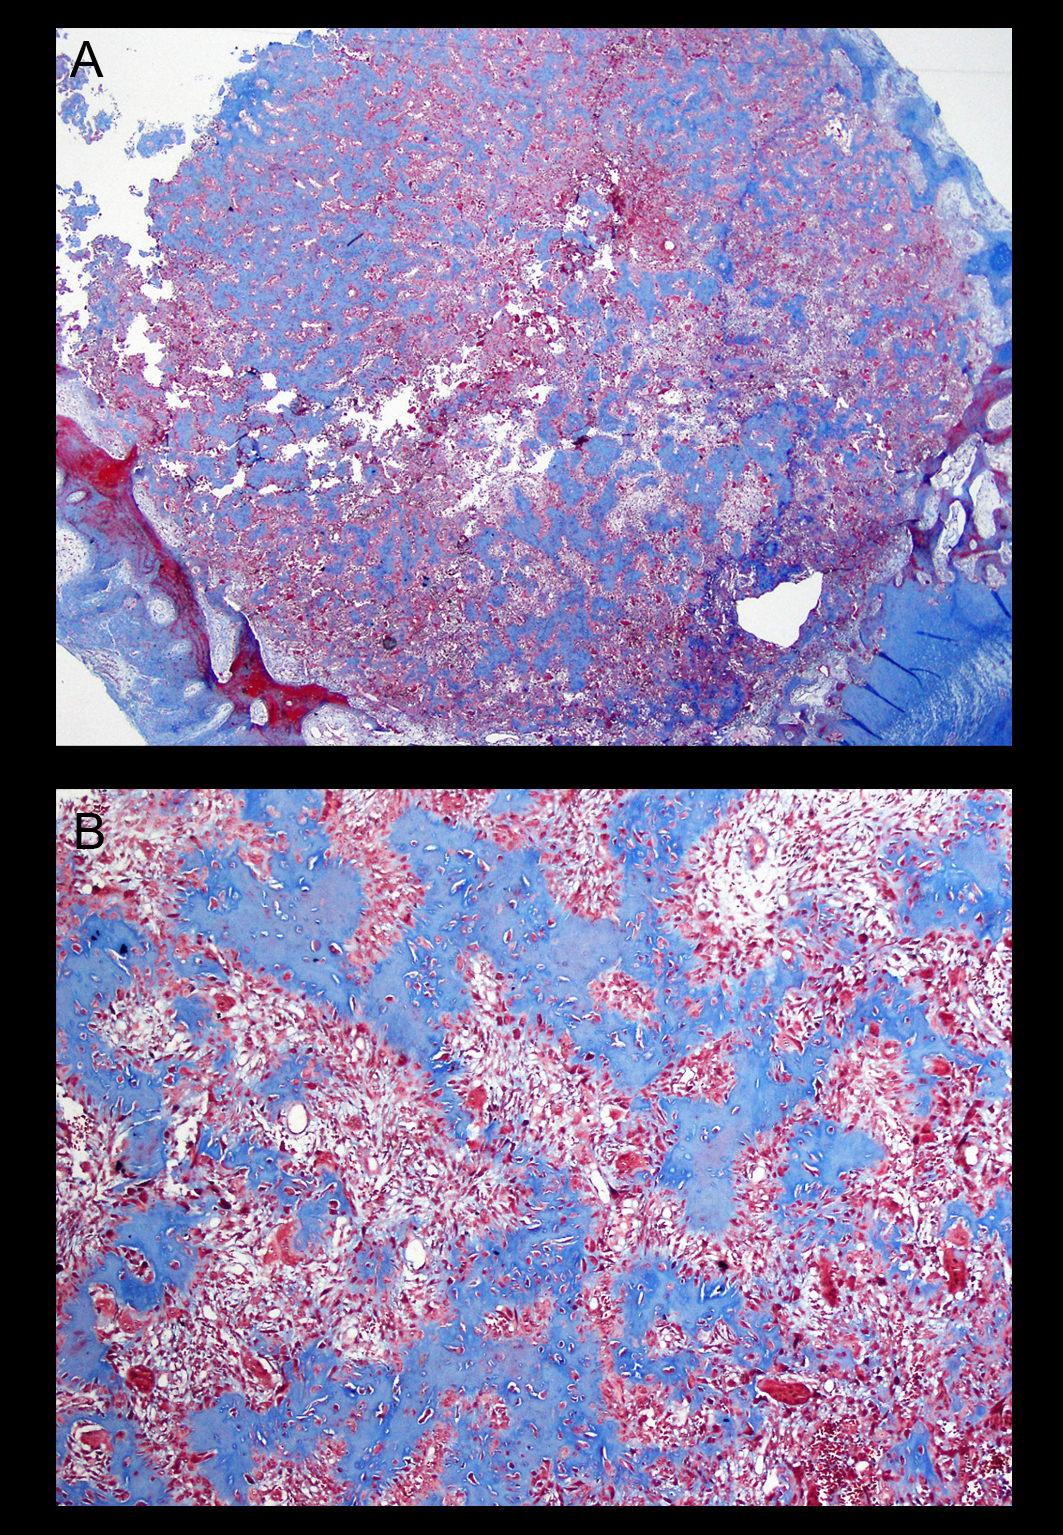

Paciente varón joven con dolor y tumefacción en el dorso de la mano de un año de evolución, refractario al tratamiento médico. Las pruebas complementarias mostraron una tumoración lítica en el hueso ganchoso con características no agresivas. Fue tratado mediante curetaje y relleno con injerto autólogo de cresta ilíaca. El estudio de anatomía patológica diagnosticó que se trataba de un osteoblastoma.

El resultado fue satisfactorio, con desaparición total del dolor e imagen radiológica de restitución completa del defecto óseo, sin signos de recidiva a los 4 años.